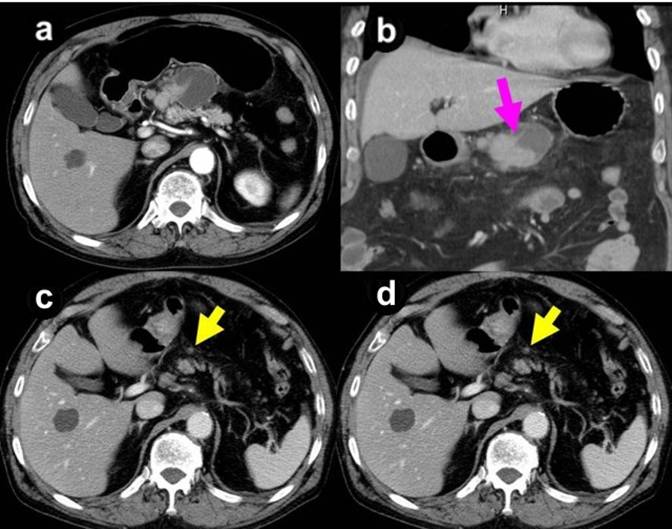

A 71-year-old male was referred with a chief complaint of abdominal distention and a mild elevation of transaminase in December 2008. CT demonstrated a cystic lesion with a diameter of 3.5 cm, which originated from the neck of the pancreas and had solid nodules inside. Several well-enhanced nodules were observed surrounding the main tumor (Figure 1ab). The main pancreatic duct was not dilated. A small amount of ascites was shown, which was preoperatively controlled with diuretics. Positron emission tomography showed no abnormal uptake, which is considered to indicate that it was unresectable (data not shown).

Figure 1. CT scan prior to (a. b.) and during chemotherapy (c.), and prior to operation (d.). |

S-1 was used as palliative chemotherapy. 80 mg/m2 per day was given to the patient for 4 weeks with a break of two weeks as a cycle. After one cycle of S-1 monotherapy, CT scan showed remarkable shrinkage of the main tumor and peritoneal dissemination (Figure 1c). This effect demonstrated by CT scan continued until four courses of S-1 administration over five cycles (Figure 1d). In addition, chemotherapy was well tolerated and no severe complications were observed. We decided upon operative re-exploration with the aim of radical resection.